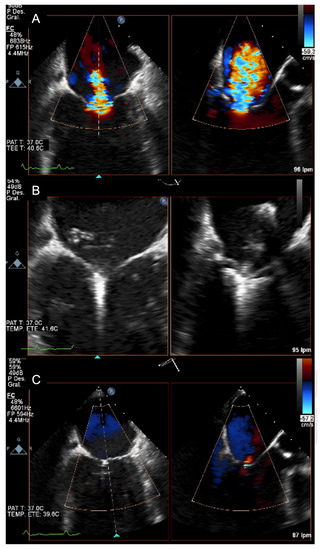

5. Diagnosis